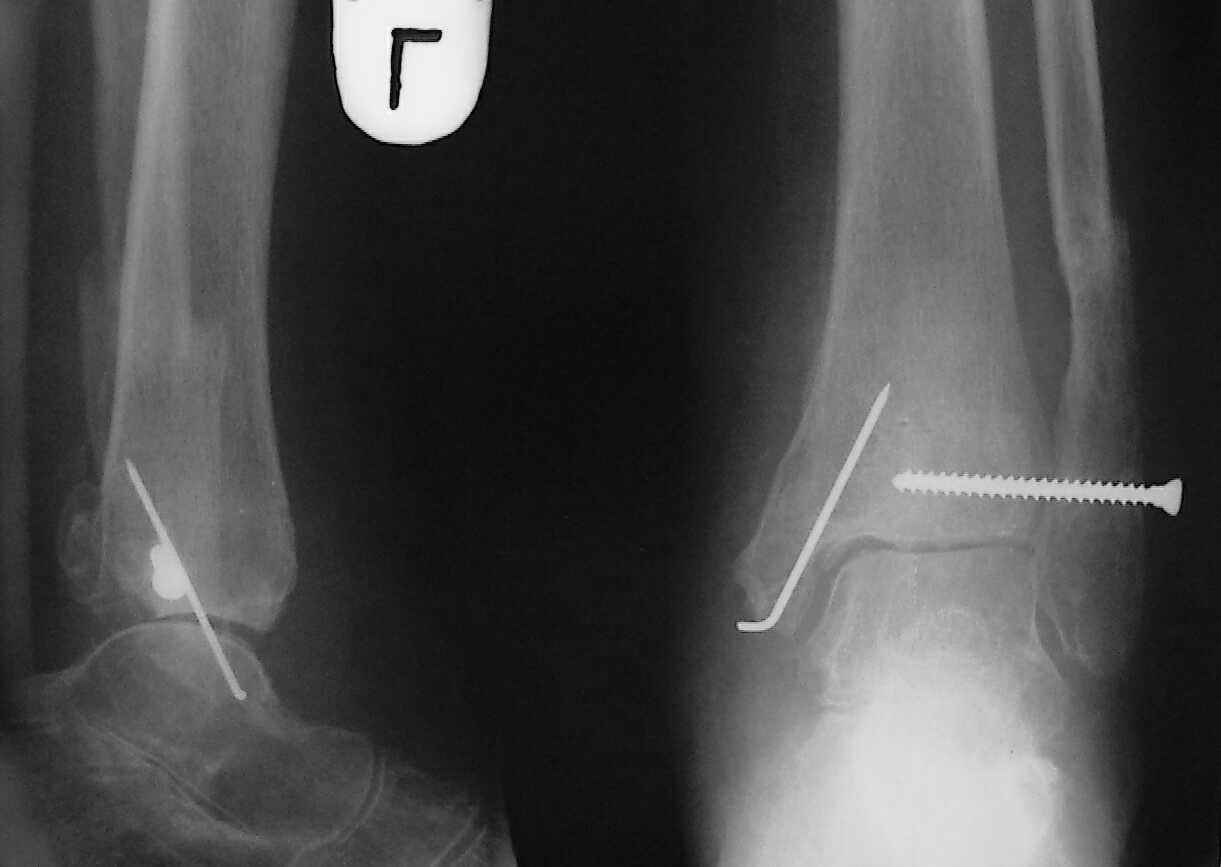

Больная 1936 г.,травма 15 ноября 2003,закрытый трехлодыжечный перелом г/стопного сустава, сахарный диабет.

При поступлении - закрытая репозиция, повторная в связи с большим отеком через неделю, подготовлена к остеосинтезу в первых числах декабря. Заживление без осложнений. Циркулярный гипс - 7 недель, снят,часть спиц удалено 20 февраля т.к.пальпировались под кожей, постепенная нагрузка, проблем нет до середины апреля когда появильсь боли с мед. стороны сустава и локалная гиперемия ( трактовалась как флеботромбоз). Повторное поступление 15 апреля - усиление болей,пов. температура, локально выраженная гиперемия.Локально выделений нет. На RTG - деструкция в области мед лодыжки и заднего края. Сахар крови умеренно повышен. Как трактовать проблему, какой диагноз и тактика лечения? Заранее спасибо, Владимир.

Ретроспективно, на Ваш взгляд, что изменилось бы при остеосинтезе более массивными имплантами?(выбор в пользу спиц как раз и был из-за минимального объема оставляемых имплантов) Иммобилизация 7 недель это очень длительно? Результат на 4 RTG - в чем нефункциональность? - согласен, что репозиция заднего края не была достигнута. Какие признаки ложного сустава мед. лодыжки ?